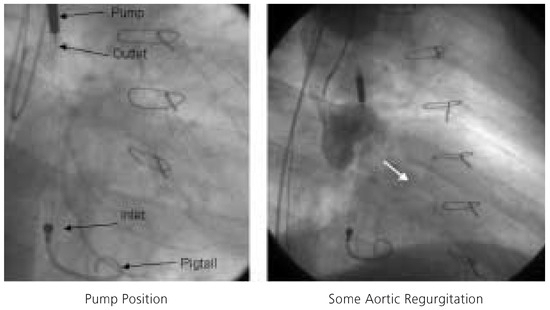

Impella Assisted High Risk Percutaneous Coronary Intervention

by Stephan Windecker and Bernhard Meier

Cardiovasc. Med. 2005, 8(5), 187; https://doi.org/10.4414/cvm.2005.01098 - 27 May 2005

Percutaneous left ventricular assist devices provide temporary circulatory support as bridge to recovery or heart transplantation in case of severe left ventricular failure and during percutaneous high-risk revascularisation procedures. We describe the first Swiss case of a high risk percutaneous coronary intervention assisted [...] Read more.

Percutaneous left ventricular assist devices provide temporary circulatory support as bridge to recovery or heart transplantation in case of severe left ventricular failure and during percutaneous high-risk revascularisation procedures. We describe the first Swiss case of a high risk percutaneous coronary intervention assisted by a new, percutaneously inserted left ventricular assist device: the Impella Recover® LP 2.5 pump. Full article

Show Figures

Figure 1